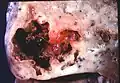

Lung abscess is a type of liquefactive necrosis of the lung tissue and formation of cavities (more than 2 cm)[1] containing necrotic debris or fluid caused by microbial infection.

This pus-filled cavity is often caused by aspiration, which may occur during anesthesia, sedation, or unconsciousness from injury. Alcoholism is the most common condition predisposing to lung abscesses.